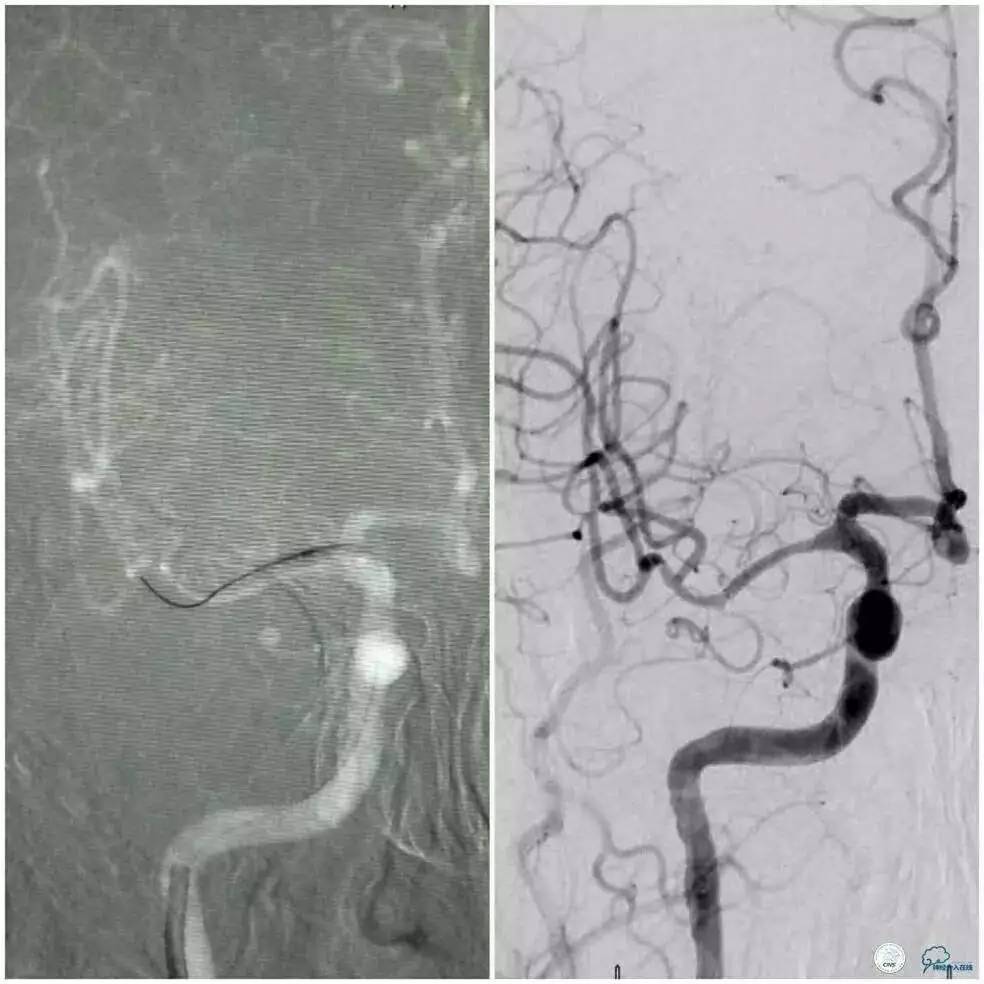

术中于右大脑中动脉M1段置入无Tip的Enterprise支架(4.5 mm×22 mm)1枚,释放后显示狭窄明显改善,前向血流3级(图3)。

半年后复查DSA示右侧大脑中动脉支架内血流通畅,前向血流3级(图4)。